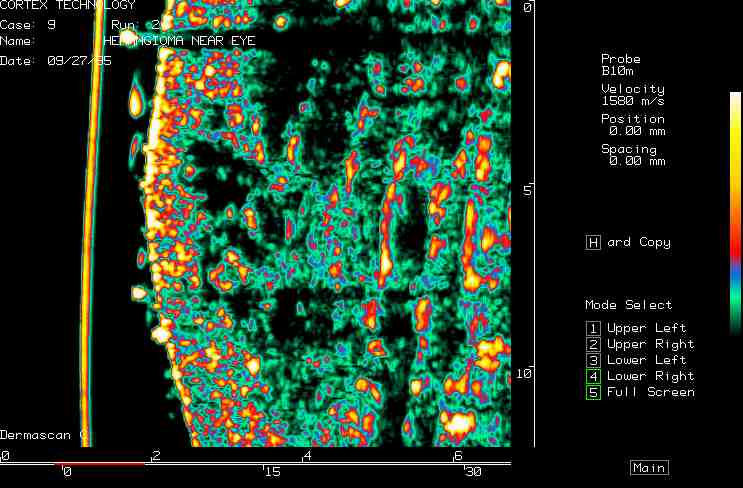

| Vascular lesions |  Port wind stain |

Hemangioma, nose |

Facial hemangioma 1 |

Facial hemangioma 2 |